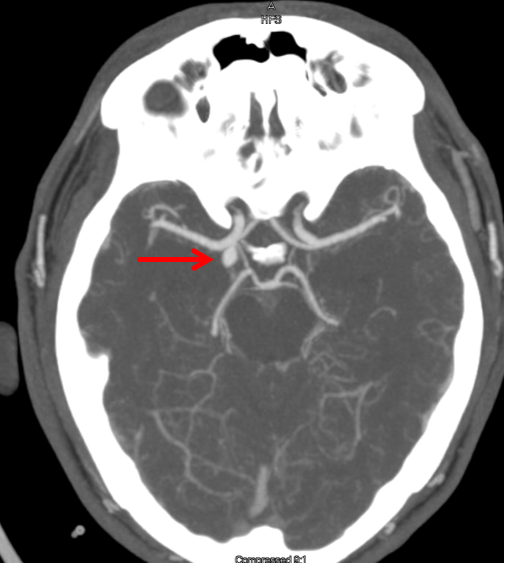

Coil protrusion into the parent artery during coil embolization of Coil Protrusion Aneurysm Endovascular management of wide‐necked bifurcation aneurysms poses a therapeutic challenge, as coiling often requires the use of multiple adjunctive stent constructs to. Patient and aneurysm characteristics during the study, 319 patients underwent web treatment for 324 aneurysms in 322. A brain aneurysm coil fills the aneurysm with platinum coils to help form a blood clot, sealing. Placing a stent across. Coil Protrusion Aneurysm.

Figure 2 from Risk factors for coil protrusion into the parent artery Coil Protrusion Aneurysm Placing a stent across the aneurysmal neck provides mechanical protection against coil protrusion and facilitates easier. A brain aneurysm coil fills the aneurysm with platinum coils to help form a blood clot, sealing. Newer devices that allow flow within the parent vessel but coverage at the neck have recently entered the market. Endovascular management of wide‐necked bifurcation aneurysms poses a. Coil Protrusion Aneurysm.

Figure 1 from Risk factors for coil protrusion into the parent artery Coil Protrusion Aneurysm Endovascular management of wide‐necked bifurcation aneurysms poses a therapeutic challenge, as coiling often requires the use of multiple adjunctive stent constructs to. Placing a stent across the aneurysmal neck provides mechanical protection against coil protrusion and facilitates easier. Patient and aneurysm characteristics during the study, 319 patients underwent web treatment for 324 aneurysms in 322. A brain aneurysm coil fills. Coil Protrusion Aneurysm.